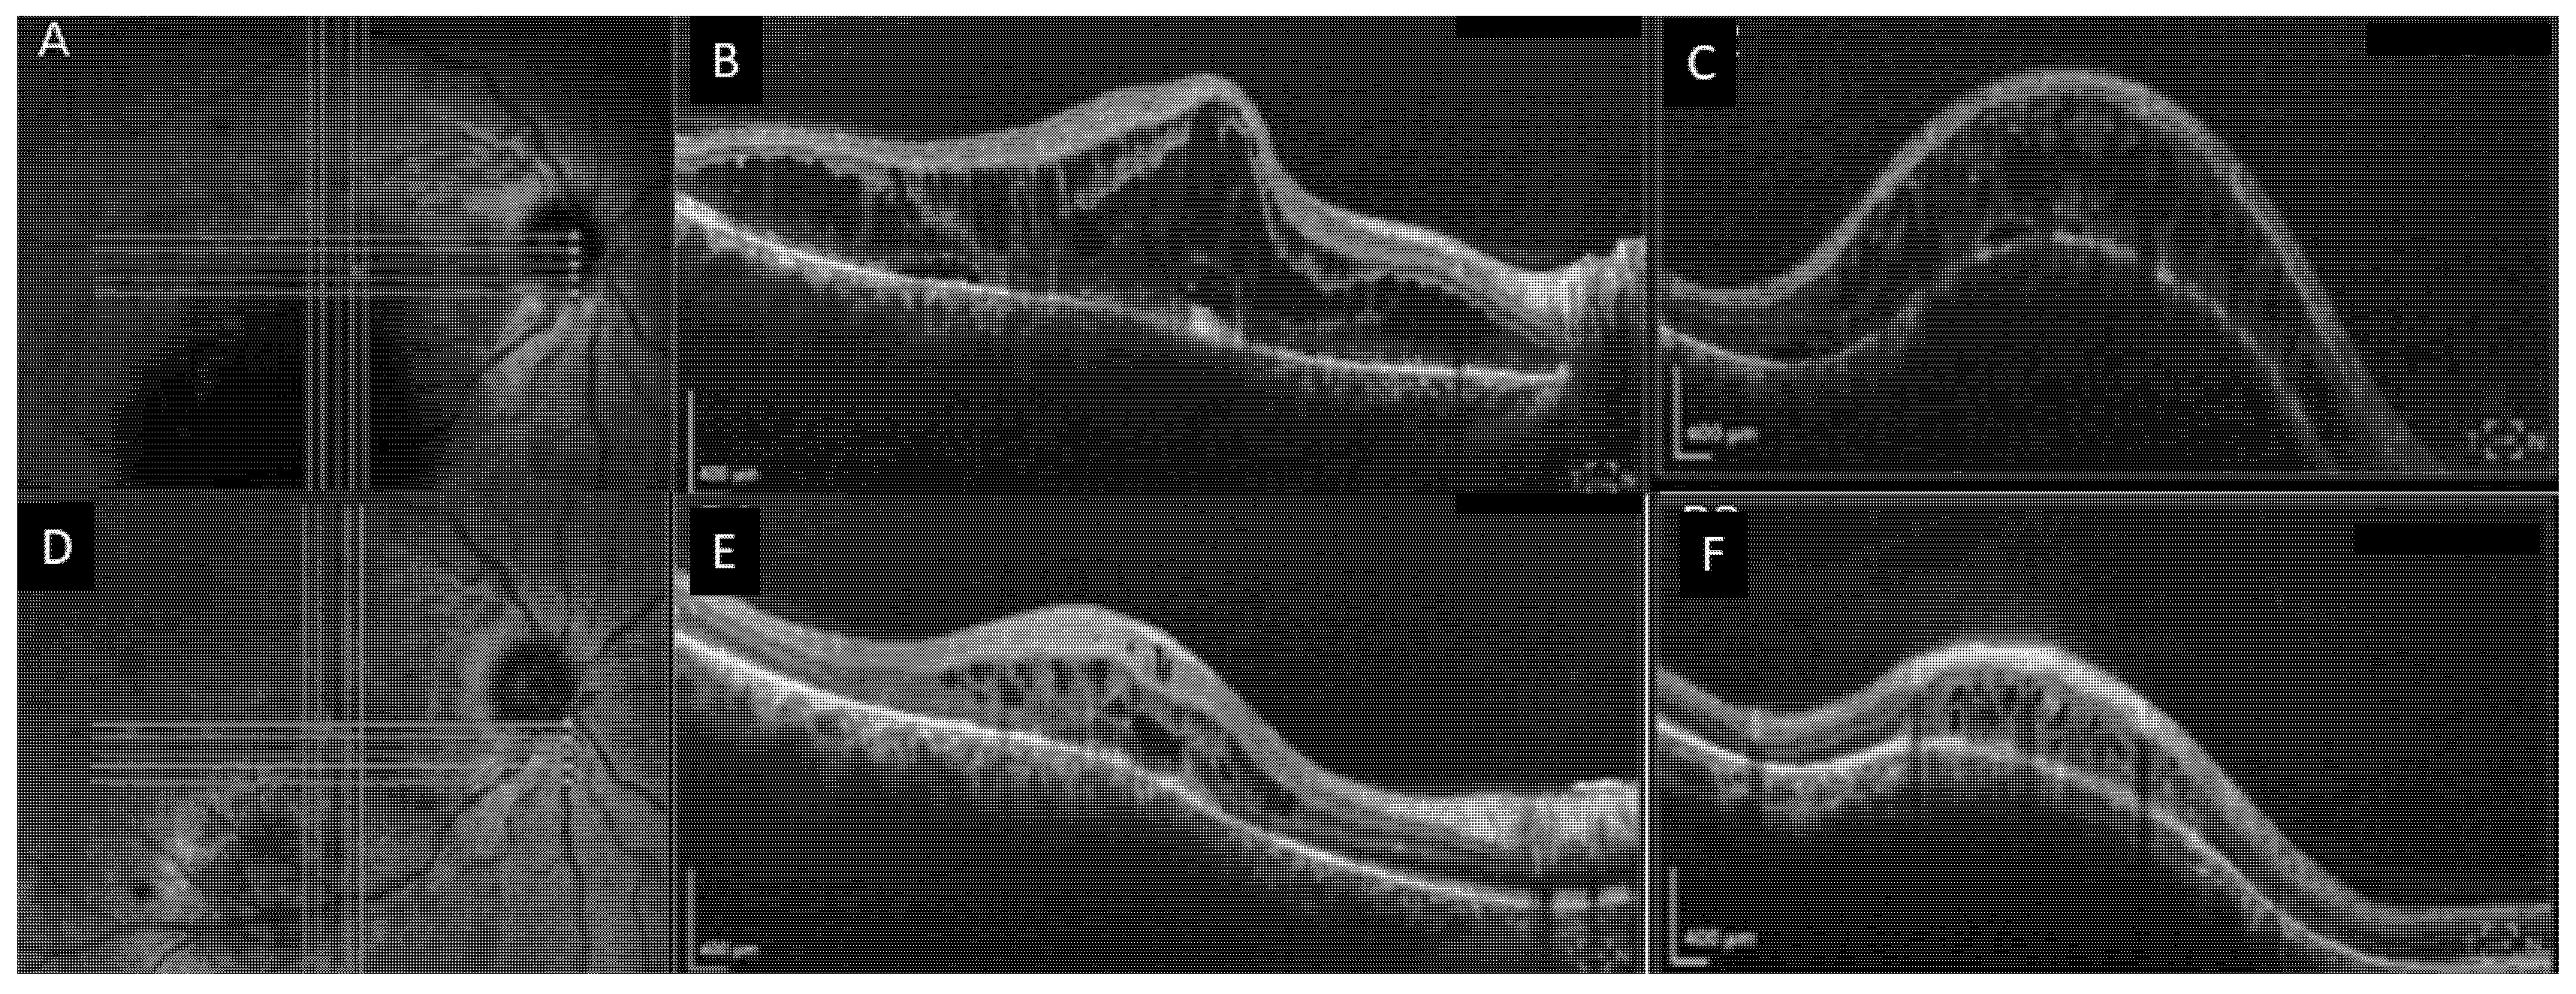

2. Case Number 1

3. Case Number 2

4. Case Number 3

5. Case Number 4